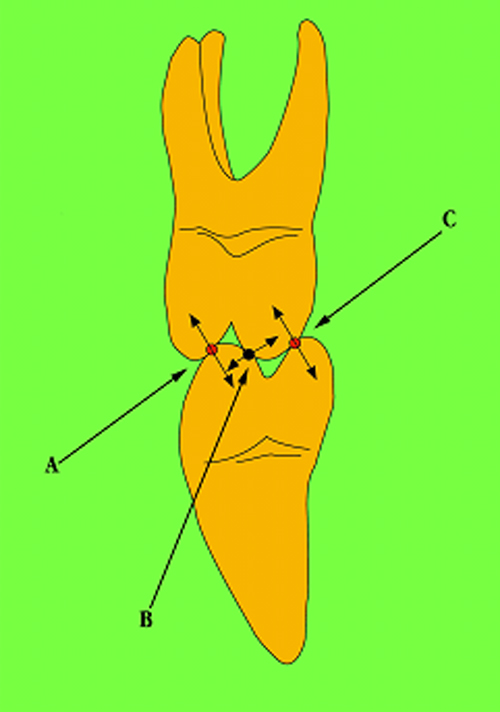

En ciertas áreas del saber humano, el lenguaje confuso o criptográfico Muchas son las técnicas elaboradas para lograr un desgaste selectivo, y numerosos autores han expuesto en su momento variadas formas de lograr una función oclusal fisiológica mediante el ajuste de la misma. Han pasado años desde entonces y, sin embargo, aún hoy, un altísimo porcentaje de profesionales “navega” por el mar de la confusión oclusal, dada la diversidad de conceptos y escuelas, sin lograr arribar a costa alguna donde poder anclar un conocimiento sólido sobre cómo tratar la oclusión Ya se esté realizando una simple obturación, endodoncia, incrustación, radectomía u ortodoncia, la lógica pocas veces, en la mayoría de los casos, vincula un tratamiento con otro, siendo el resultado final el mismo caos inicial; enmascarado por mucho tratamiento profesional. El ajuste oclusal es un medio inicial de proveer al sistema enfermo de: Dicha técnica, que puede ser terapéutica en sí misma; consta de dos etapas, a saber: 1) Ajuste Oclusal por Adición Mediante el estudio de la guía anterior, encargada de efectuar las Disclusiones durante las excursiones mandibulares, podremos observar si ésta es funcional o no. • Marcas de carácter continuo, si en ese recorrido se produce la Disclusión de los sectores posteriores y todo marcha correctamente. FIG 1-2 Si por el contrario observamos: • Marcas de carácter discontinuo, significa que dicha Disclusión se está efectuando por medio de una pieza dentaria posterior a la guía anterior. FIG 3-4-5 (FIGS. 3, 4 Y 5). En la figura 6 las flechas indican, en un caso clínico de análisis oclusal, la presencia de marcas discontinuas que indican Interferencias en Propulsiva. FIG 6-7 Y por último, si existieran: • Abrasiones de las áreas discluyentes en las áreas de diagnóstico de la guía anterior, deberemos aportar material a dicha zona para no permitir el choque lateral de las piezas posteriores (Ajuste Oclusal por Adición) En las imágenes 11 y 12 podemos observar la adición de composite en la punta de un canino derecho, previa la observación de la Faceta Parafuncional remarcada durante el análisis oclusal en el articulador. (FIGS. 8 A 12). 2) Ajuste oclusal por Sustracción o Desgaste Habiendo cumplido ya con la verificación de la funcionalidad de la Guía Anterior, comenzamos los desgastes en céntrica, a fin de lograr un único arco de cierre, guiado eficazmente por la Guía Anterior; es decir: la coincidencia entre Oclusión Habitual y Oclusión en Relación Céntrica. En este caso, intentar gastar dichos puntos, de ser posible sólo en las cúspides de corte o no fundamentales: • Crestas Triangulares Internas, Cúspides Vestíbulares Superiores • y un poco de las Crestas Triangulares Internas, Cúspides (FIGS. 13 A 16). Si la deflección es hacia el lado opuesto, se invierten los desgastes. En las migraciones hacia adelante, las únicas razones posibles están en los puntos estabilizadores (FIG. 17); es decir: -Vertientes Distales de los Rebordes Marginales, Triangulares (FIG 17) (FIG 18 A-B-C-D) Obsérvese cómo, en una boca prácticamente entera, comienzan a “desmoronarse” prismas adamantinos (FIG. 19), como consecuencia de un punto prematuro de contacto, ubicado en la posición de un estabilizador, que provoca la discrepancia horizontal postero-anterior causante de dicho efecto (FIG. 20). FIG 19-20 Dicho punto, será necesario ajustarlo antes de cualquier tratamiento en la zona ¿Cuáles serían las consecuencias si esos incisivos fueran implantados tal como es frecuente observar en múltiples congresos y cursos de implantología, donde el tema de la oclusión no es más que un cuadro polifacético y anecdótico? 14 15 16 17 Todo producto del adelantamiento mandibular Realizados ya los desgastes en céntrica, obteniendo de esta manera un único arco de cierre, es decir, oclusión en relación céntrica, debemos realizar el ajuste de las excéntricas, apoyando la acción de la guía anterior, para lo FIG 22 a. De un lado a otro de un mismo maxilar, la imagen es especular, o sea invertida. b. En hemimaxilares cruzados, la imagen es idéntica. Allí donde existan colisiones entre cúspides, se deberá crear un surco para que dicha cúspide antagonista migre a su través, tanto en el lado de no trabajo, como en el de trabajo y en el de propulsión. FIG 23 Es importante conservar esta parte del surco, ya que si no existieran, los contactos entre cúspides serían en superficie y no puntiformes (fig. 24). FIG 24 1. Obtener un único arco de cierre con coincidencia entre oclusión habitual y relación céntrica. 2. El cierre mandibular debe ser recibido sólo por la tabla premolar-molar. 3. Durante las excursiones funcionales es la guía anterior la que debe sufrir las fuerzas laterales. 4. De cumplirse estas dos premisas debemos obtener libertad de desplazamiento (no confundir con libertad en céntrica) a las piezas posteriores mediante la creación de surcos disclusivos. Examinadas ya las posibles migraciones mandibulares y los desgastes o aposiciones necesarios para poder ocluir en céntrica, es fundamental recordar que, previamente a todo tipo de ajuste, se ha hecho necesario ubicar a la mandíbula en relación céntrica. Para ello debemos utilizar el propio funcionalismo muscular 22 FIG 25 Y esto no significa otra cosa que: piezas dentarias estables en todos los planos del espacio, ATM centrada en la cavidad glenoidea, periodontos sin tensión, músculos en la dimensión de elongación adecuada para un fisiologismo Paz absoluta en la intimidad del Sistema Estomatognático. Y así, como corolario final, es posible establecer una regla de oro similar en importancia a la conocida formula: Forma = Función Ésta es: FIG 26 FUNDAMENTOS NEUROFISIOLÓGICOS DEL REGISTRO DE OCLUSIÓN EN RELACIÓN CÉNTRICA ( ORC) MEDIANTE EL USO DE LAMINILLAS DE LONG CUADRO

Durante estos procedimientos es importante no gastar los topes y además crear, redondeando superficies, los estabilizadores y los A, B y C.

Sintetizando aún más estas pocas reglas, ajuste oclusal es: